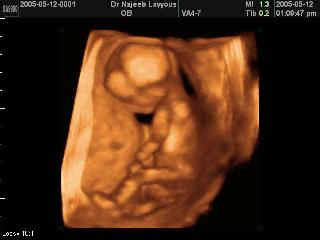

“You can see the baby moving. When you perform an abortion under sonography, you see the baby move away when the instruments are inserted into the vagina.”

She describes how an unborn baby struggles to feed the abortion instruments, as seen on the ultrasound screen. Watch an ultrasound of an abortion here. Read more about Carol Everett. read Abby Johnson’s story of seeing an unborn baby fighting for his life during an ultrasound guided abortion.